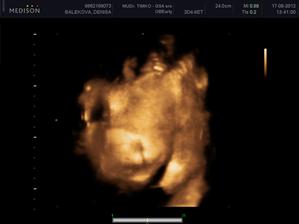

Nas anjelik Alex

Zatial este schovany v brusku ale uz coskoro sa z neho potesime aj nazivo 🙂) Lubime nasho Alexa uz od sameho zaciatku 🙂